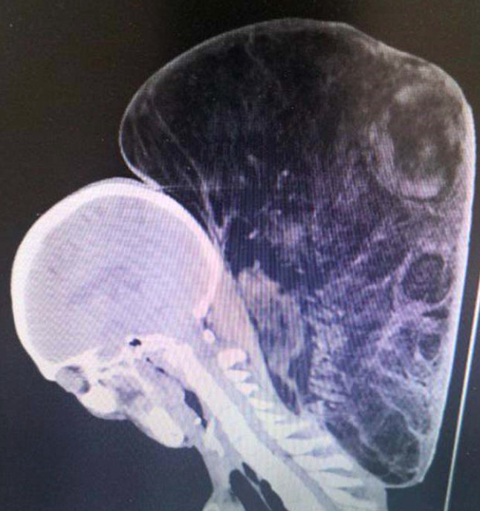

Galerinin tamamı için tıklayınızBüyük tümörün 100 cm veya 40 inç bir çevresi vardı. Dr. Dong, çalışma hayatı boyunca hiç bu kadar büyük bir tümör görmediğini söyledi.

Büyük tümörün 100 cm veya 40 inç bir çevresi vardı. Dr. Dong, çalışma hayatı boyunca hiç bu kadar büyük bir tümör görmediğini söyledi.